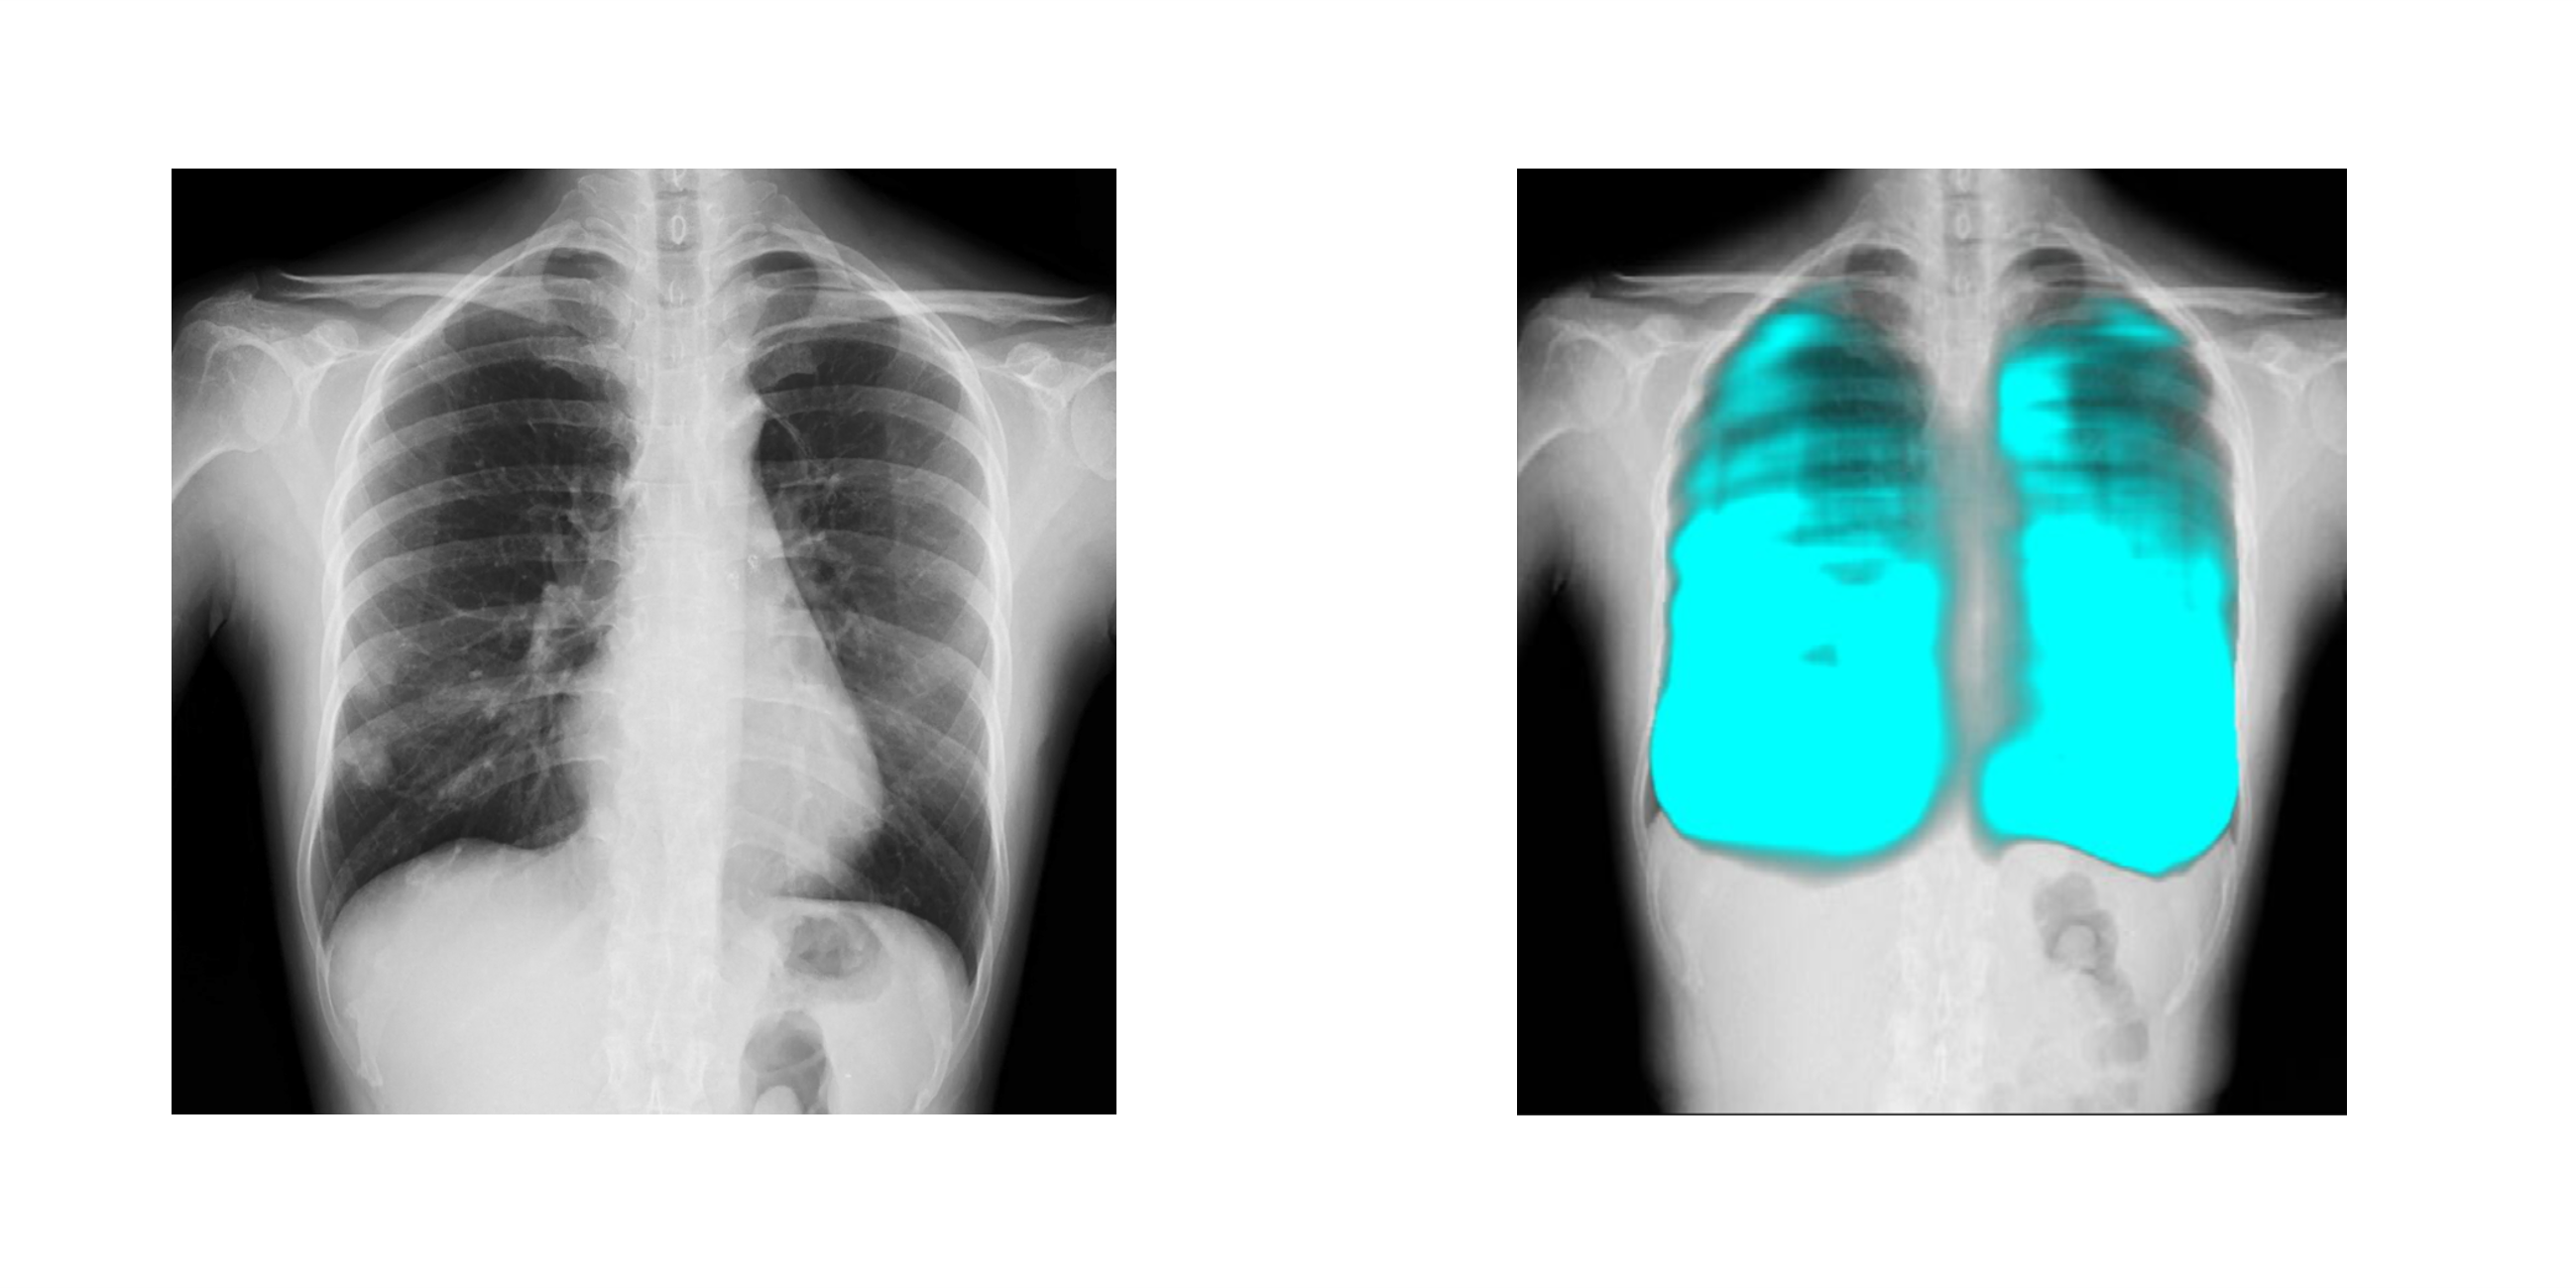

コニカミノルタのX線動態解析技術/イメージングAI技術と、FPTの高度なAI技術を活用し、呼吸器疾患の診断支援、医療レポートの自動生成など新しい診断技術の確立を目指します。コニカミノルタ独自のX線動態解析は、世界で300件以上の特許を取得しており、既に400台以上の販売実績があります。ベトナムの医療イノベーションとデジタル変革による呼吸器疾患対策を推進することで、国民の健康と医療従事者の負担軽減に貢献します。

• 簡易かつ高度なX線動態解析画像を用いた呼吸器疾患に関する医療指標の開発と、AI診断支援ツールの開発による呼吸器疾患の早期診断機会創出

コニカミノルタはデジタルX線動態撮影および動態解析を、新しい”動きの診断”を提供するソリューションとして展開しています。この当社独自の技術「X線動態解析」を搭載したシステムとして、一般X線撮影装置を用いて動画を撮影できるデジタルX線動態撮影システムを開発・提供しており、既に国内外の医療機関で導入実績があります。